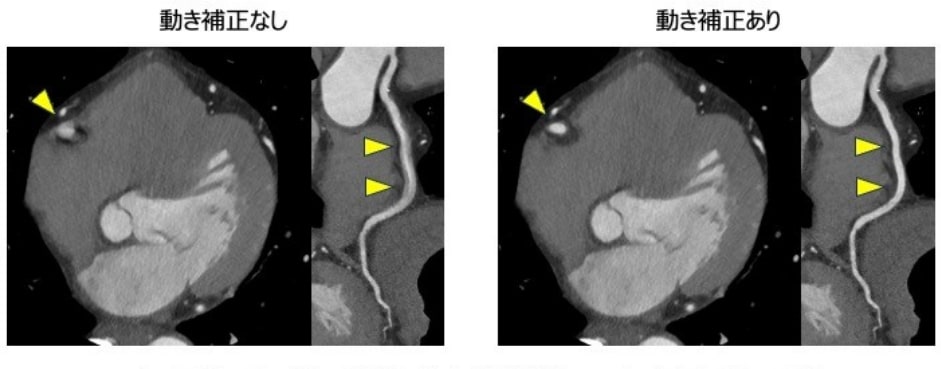

動き補正技術(CLEAR Motion Cardiac)

補正なしでは、動きの影響により冠動脈がブレてしまい評価できませんが、補正処理後の画像では、ブレがなくなり正確な評価が可能です。